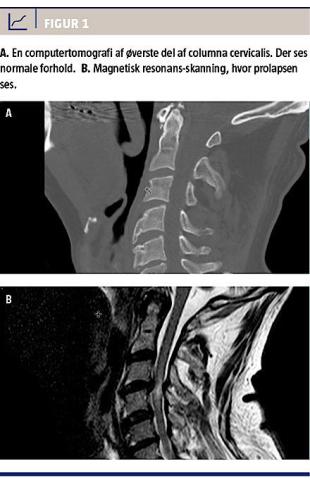

På femtedagen var der ingen fremgang. Neurologerne foreslog magnetisk resonans (MR)-skanning af columna totalis på mistanke om blødning/kontusion. Skanningen blev foretaget på tiendedagen, og den viste, at der var en traumatisk diskusprolaps på C3/C4, hvilket påvirkede medula spinalis (Figur 1).